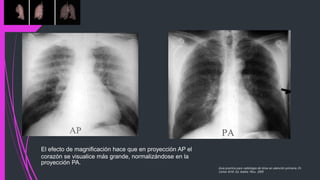

El efecto de magnificación hace que en proyección AP el

corazón se visualice más grande, normalizándose en la

proyección PA.